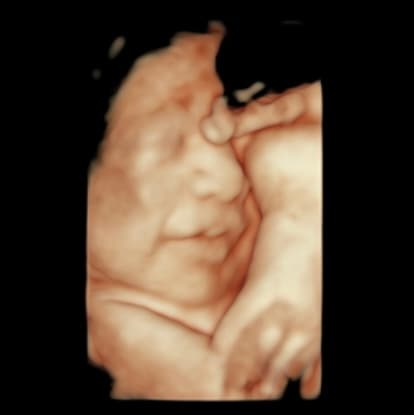

Explore our collection of ultrasound images and clinic photos. See the quality and clarity of our technology and the comfort of our facilities.

Book an appointment today and capture beautiful images of your baby. Our state-of-the-art technology provides clear, detailed ultrasound images for you to cherish forever.